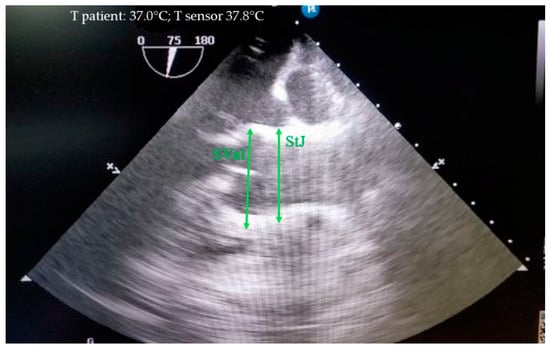

The sinus of Valsalva and the sinotubular junction were measured during diastole from the outer contour to the outer contour (Figure 3).

Figure 3. Measurement of the sinus of Valsalva (SVal) and sinotubular junction (StJ) in mini pigs from the outer contour to the outer contour during diastole.